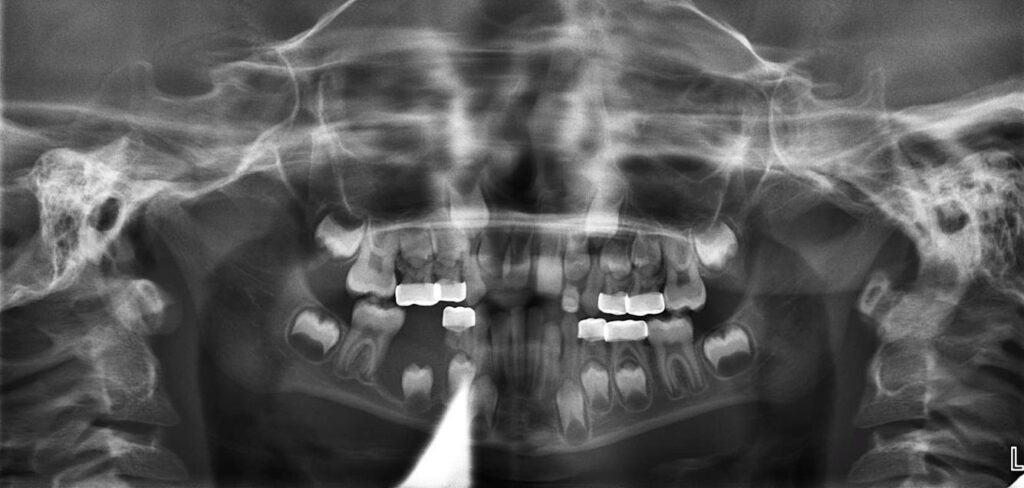

6-year-old boy with unusual radiographic finding

A 6-year-old boy with an unusual radiographic finding.